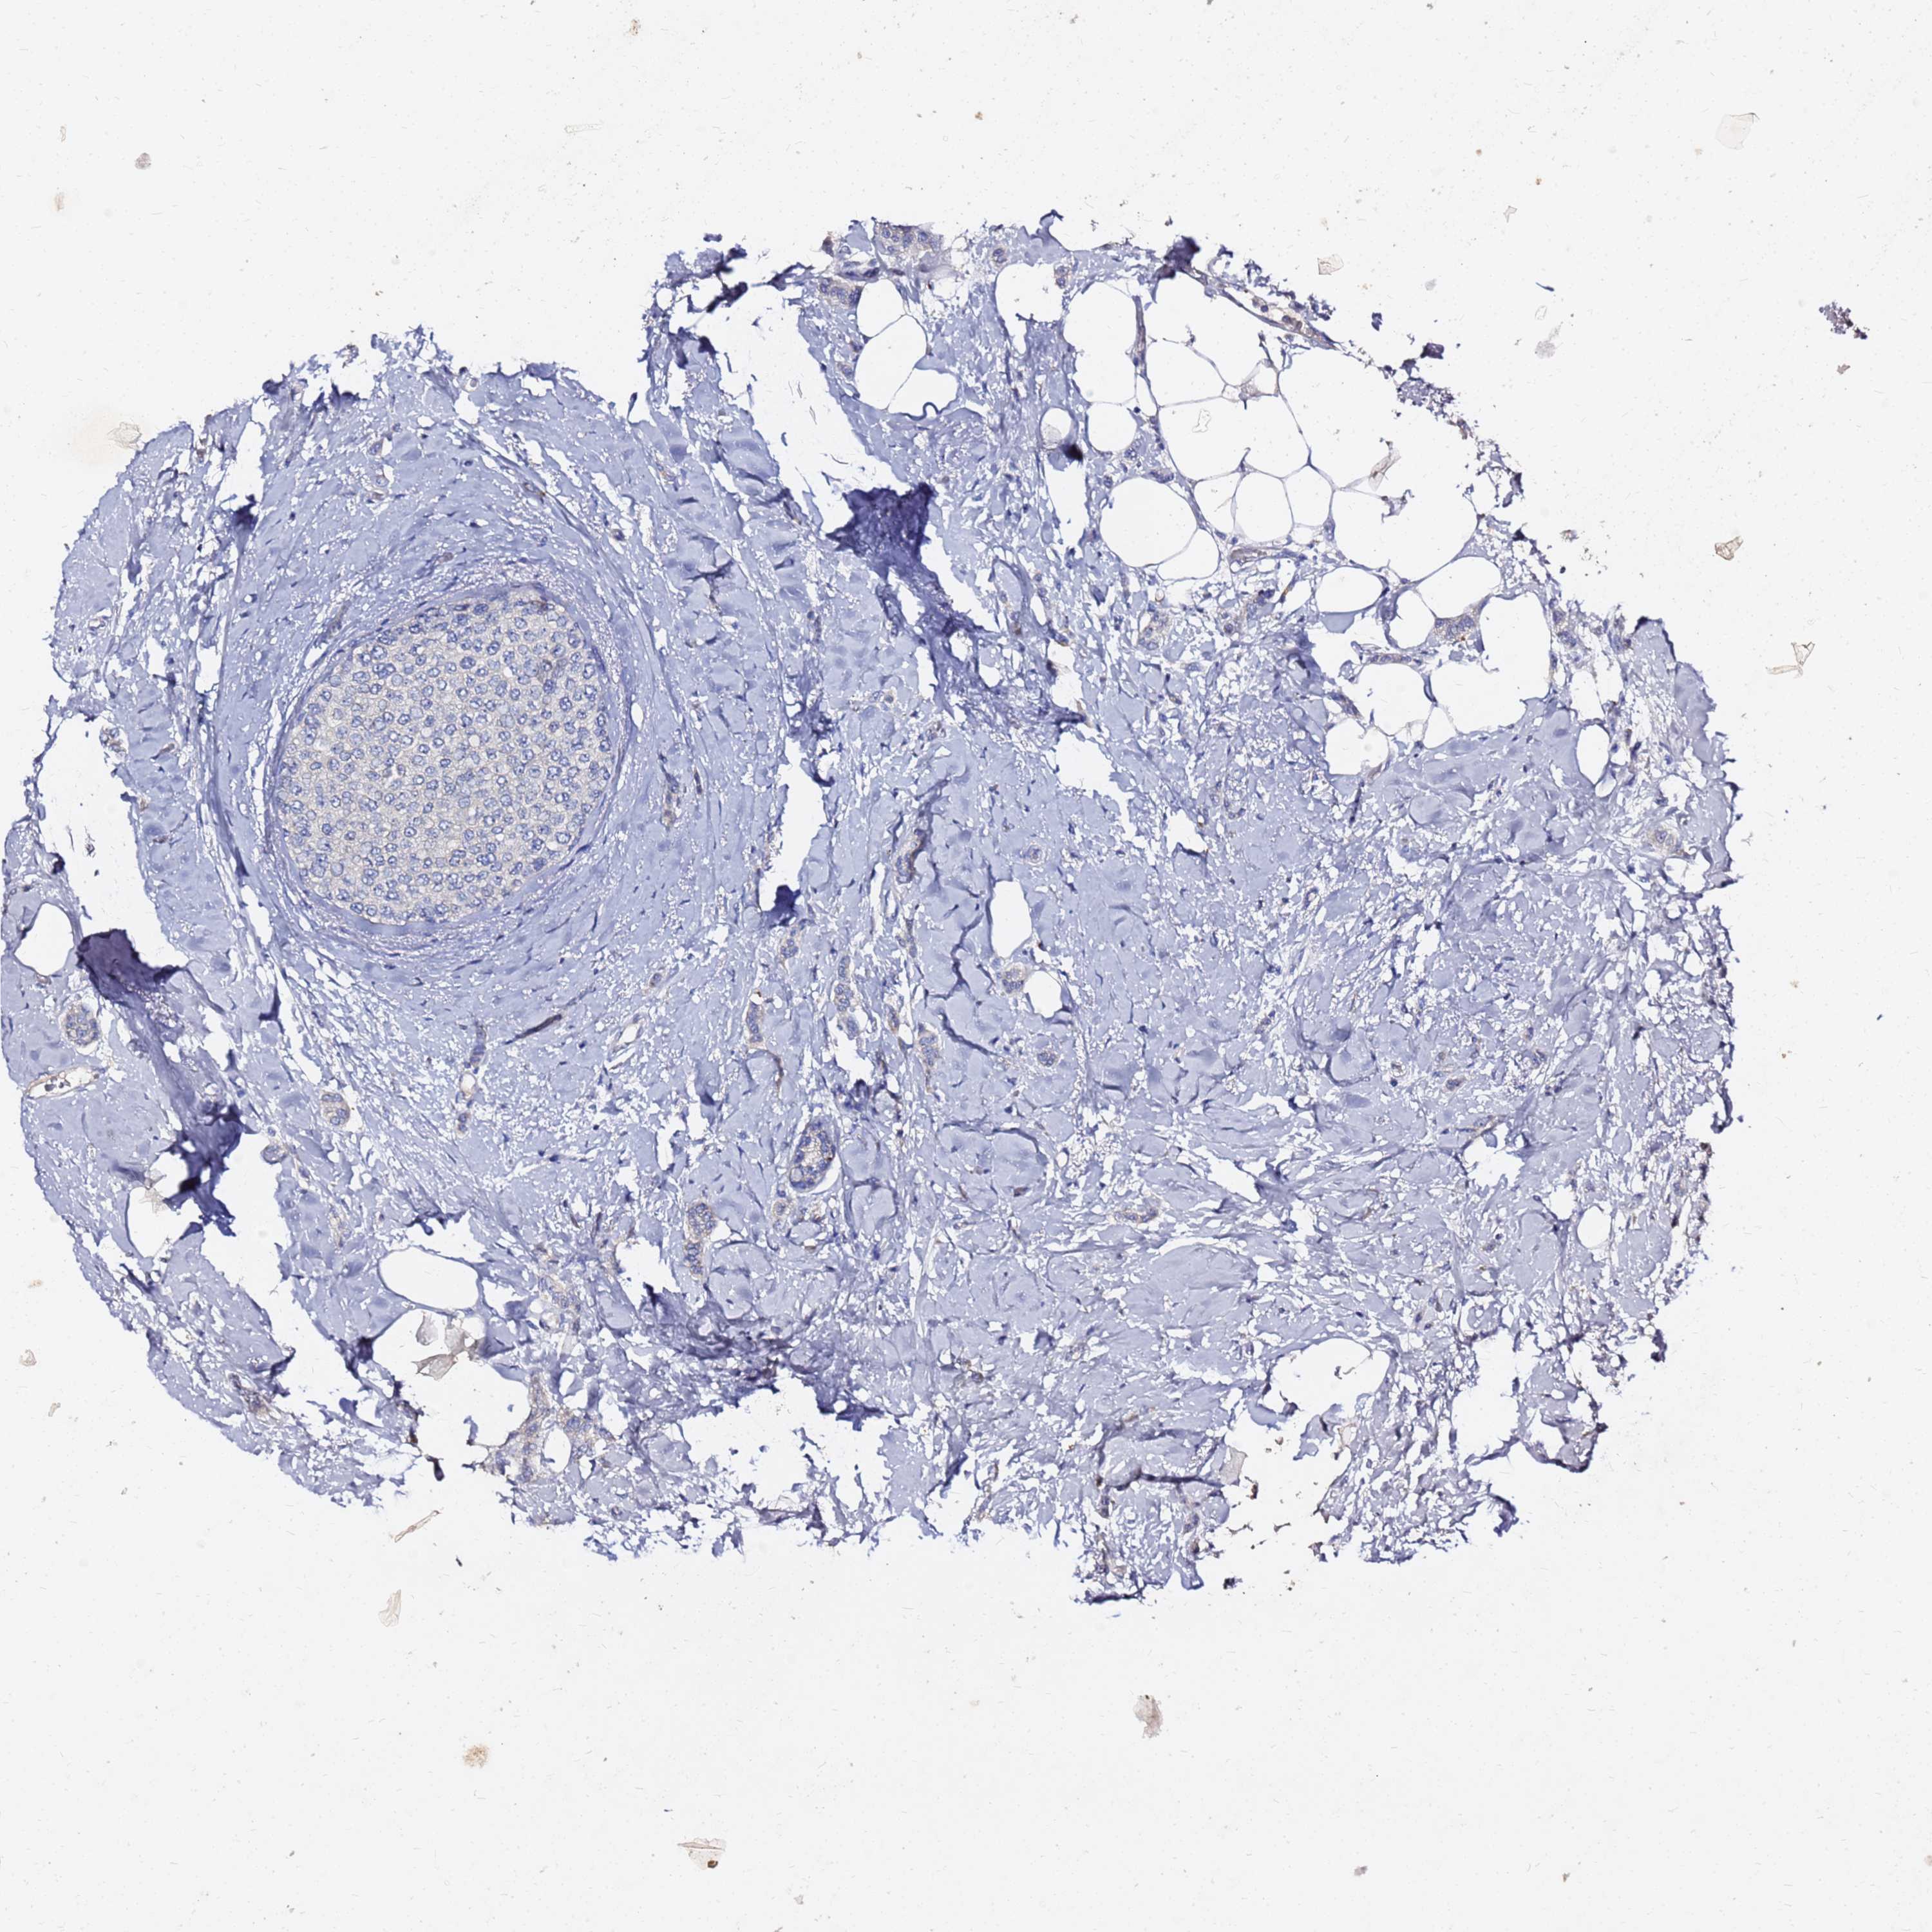

CANCER BREAST CANCER Show tissue menu

BRCA TCGA BRCA VALIDATION PROTEIN EXPRESSION

ANTIBODIES

AND

VALIDATION